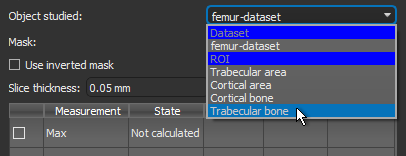

- Select the region of interest that you want to analyze in the Object studied drop-down menu, as shown below.

You should note the following:

- Moments of inertia are usually extracted from bone segmentations.

- Measurements of mean thickness (Th) are usually extracted separately from cortical and trabecular bone segmentations.

- Measurements of the periosteal perimeter can be extracted from cortical area segmentations.

- Measurements of the endocortical perimeter can be extracted from trabecular area segmentations.